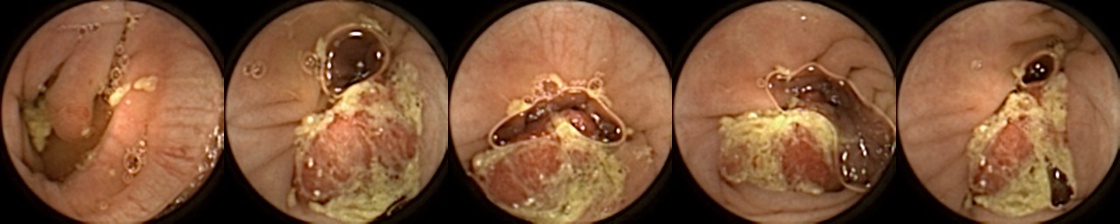

Refer to caption

Figure 1: Positive exemplar images with each row showing five images of a unique polyp, where in each row, the first image corresponds to first partial and fifth image is the last full view of the same polyp. The polyps have been marked in green for each image.

For MIV, we construct both positive and negative exemplar pairs from this multi-patient polyp image dataset. Positive exemplars are constructed based on the five images from a single polyp, with one of the second, third, or fourth image designated as the query and the remaining four images forming the target bag. Images from five example polyps are shown in Figure 1. Negative exemplars are constructed using a more sophisticated strategy: if a patient has multiple polyps, the query image is selected from one of those polyps at random, while target images are sampled from other polyps of the same patient; if a patient has only one polyp, target images are drawn from different patients entirely.